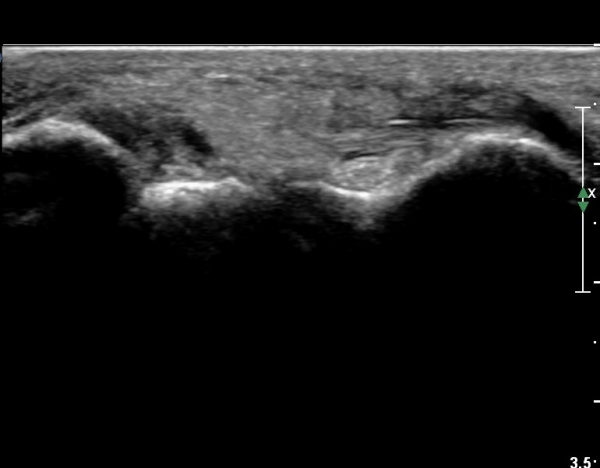

Àü¹æ¸»´ÜÁ¾°ñºñ°ñÀδë Á¾´Ü¸é°Ë»ç¿¡¼­ ƯÀÌ ¼Ò°ßÀ» º¸ÀÌÁö ¾ÊÀ½(»çÁø 1).